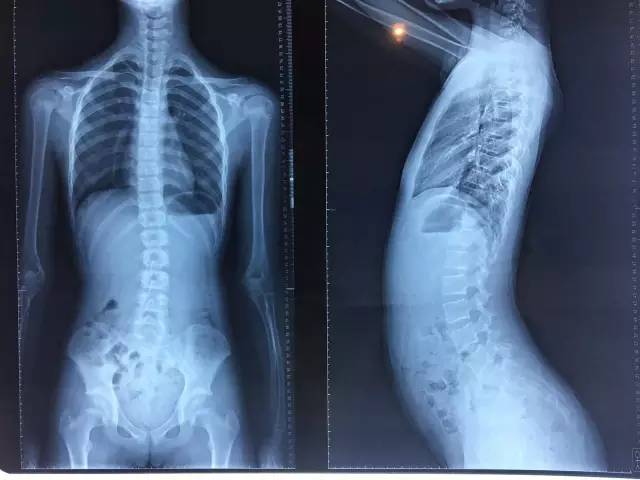

从触诊结合她之前的X光片,我发现小女孩有明显的椎寰椎旋转错位,恼人的怪病原来就是“颈椎病”,当然各人症状不同,有人表现为头晕、有人表现为头痛,调整2次后,基本恢复正常,看世界不再颠倒了。朋友非常感谢我,直呼神奇。

X光片可以看出有她有轻度的脊柱侧弯。“下交叉”姿态非常明显,腰曲过大,11岁的女生肚子向前突出,好像有了中年人的“小肚子”一样。卧位时,左侧骨盆高,右侧骨盆旋前,股骨内旋,尾骨上翘。整个人好像没有力气,“骨头发软”,只要坐下来就好像没有力气要东倒西歪。另外肠胃一直不太好,小小年纪就便秘严重。